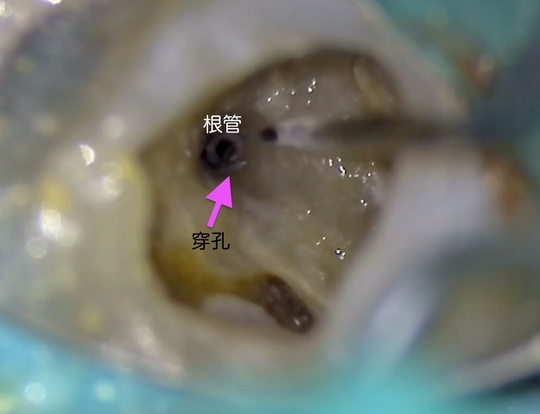

管の分かれている部分に根の治療による穿孔がありました

穿孔部分の封鎖と通常の根管治療を行いました

治療は1回1時間程度で複数回。根の壁の封鎖材料は、MTAセメント。副作用もなく穿孔部分位の封鎖には最良な材料です。そのほか、バイオセラミック系の生体活性材料も現在は使用します。マイクロスコープを使用した精密根管治療では、ラバーダムシートの使用、無菌的操作が絶対条件です。

肉眼やルーペでは見えない世界が広がります